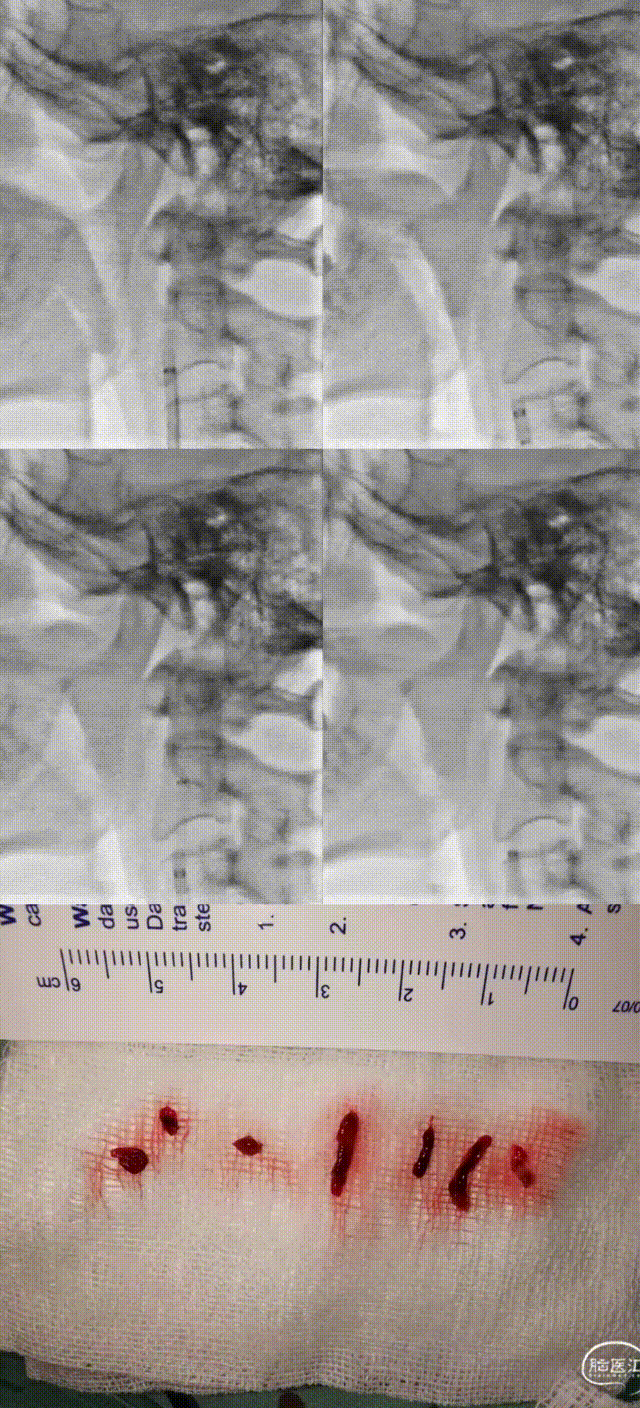

Multiple aspiration passes were performed from the C1 to C4 segment of the right ICA using Zenith Distal Access Catheter, retrieving a large volume of dark, organized thrombus. Repeat angiography revealed severe residual stenosis (~70%) at the C1 segment with a suspected dissection and poor visualization distal to the cavernous segment.